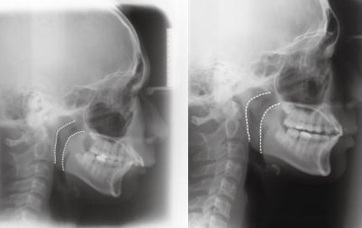

하악왜소증 치료 전(왼쪽)과 후 비교사진

김경호·최윤정 연세대 강남세브란스병원 치과병원 교정과 교수팀은 왜소한 아래턱에 성장을 촉진하는 장치를 사용해 교정치료를 받은 평균 11살 어린이 24명을 7~8년간 추적관찰한 결과 아래턱의 성장으로 턱과 치열이 교정되고 좁았던 기도가 넓어지는 것으로 나타났다고 17일 밝혔다.

치료 후 환자의 평균 기도상부 직경은 8.5㎜에서 10.5㎜, 기도하부 직경은 9.8㎜에서 11.2㎜, 전후방 골격차이지수(ANB)는 7.0도에서 5.1도로 아래턱이 성장하면서 상하부 기도의 크기와 전체 부피가 증가했다.

이는 약 2년여의 치료과정이 끝나고 계측된 수치로, 7~8년 후 성장이 완료된 시점까지 치료효과가 유지됐다. 좁았던 기도는 치료 후 확장되면서 정상 어린이와 차이가 없었다. 이같은 기도확장 효과는 좁은 기도로 인해 생길 수 있는 코골이와 수면무호흡증을 예방하는 데 도움될 것으로 기대된다.